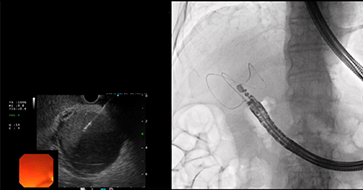

胆膵疾患では胆管の閉塞による黄疸や肝障害に対してステントを留置して胆道ドレナージを行う必要があることが多々あります。原則としてはERCPでの胆道ドレナージを試みますが、様々な理由で困難な場合に胃や十二指腸などの消化管から超音波内視鏡を用いてステント留置を行うEUS-Dを行います。

また、急性胆嚢炎に対する治療は通常は外科的切除が行われますが、全身状態が悪く手術のリスクが高い場合には、超音波内視鏡を使用した胆嚢ドレナージで治療を行います。

急性胆嚢炎で受診

超音波内視鏡下胆嚢ドレナージ

十二指腸から

胆嚢にステント留置